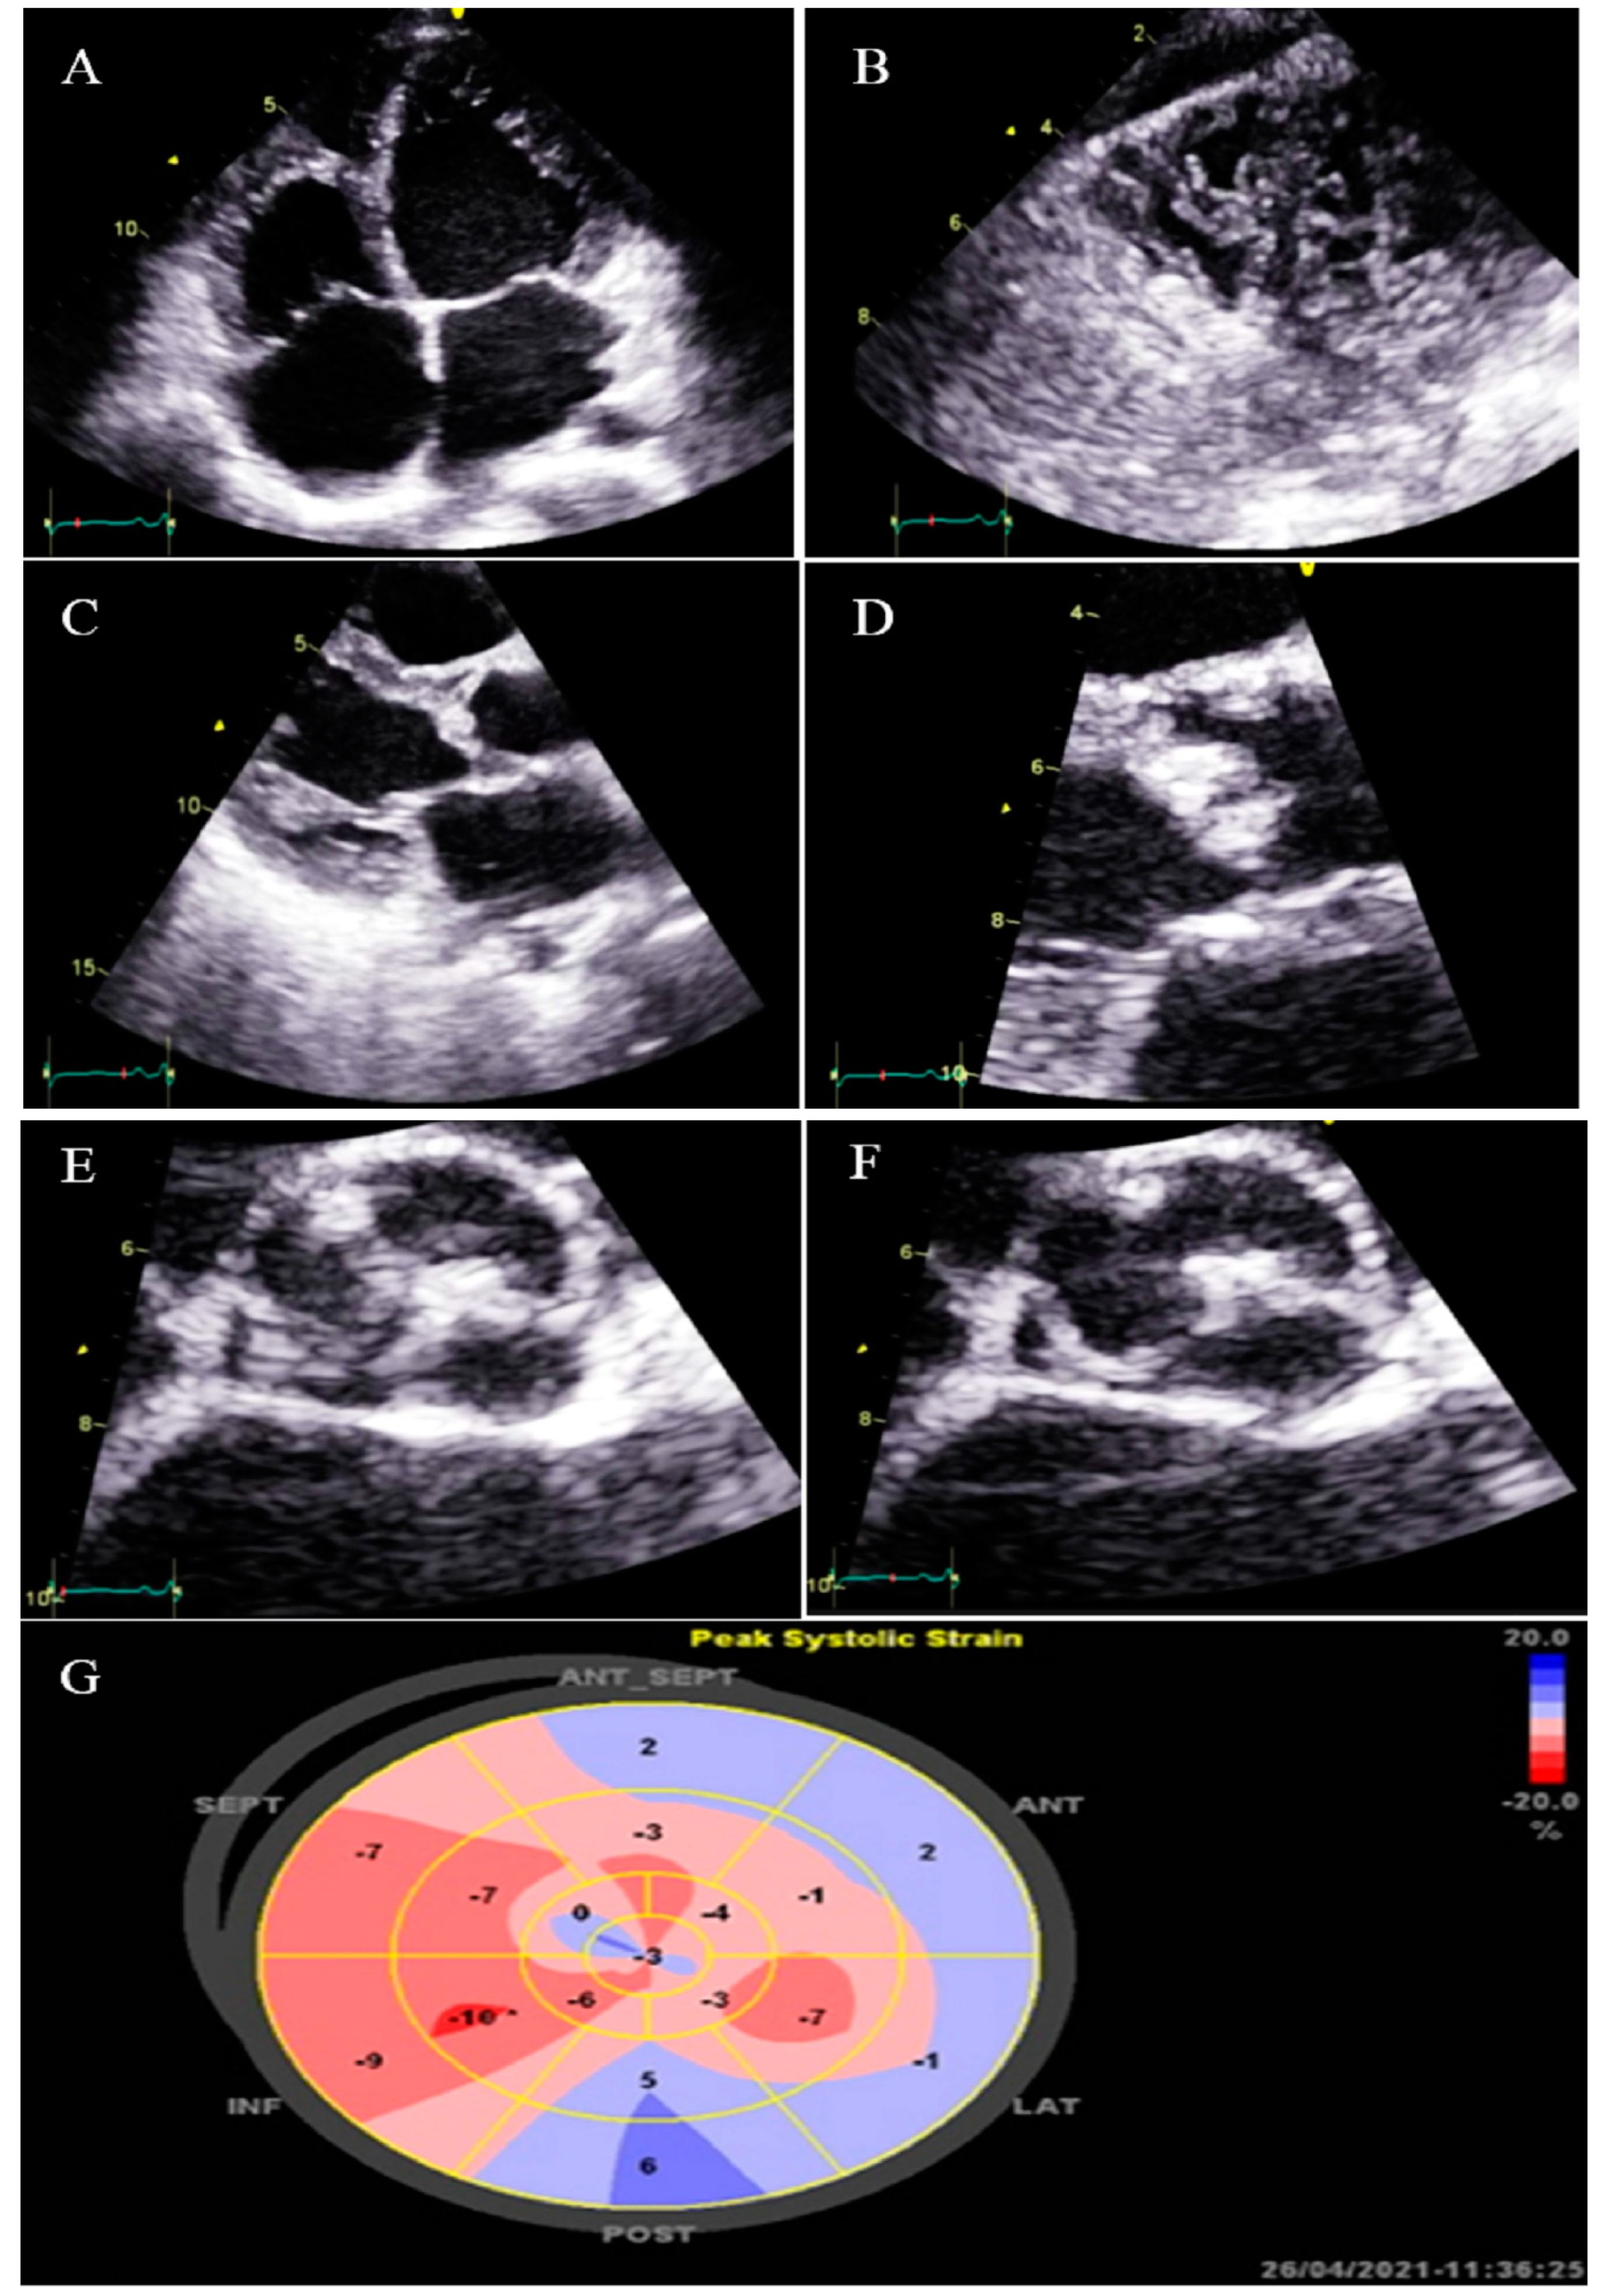

Figure 3.

Two-dimensional transthoracic echocardiographic views of case #3. (A); Left ventricular apical SAX view, illustrating hypertrabeculated apical portions in addition to deep intertrabecular recesses. (B); Color Doppler echocardiography, showing evidence of direct blood flow from the ventricular cavity into deep intertrabecular recesses. (C); Dilated aortic proximal ascending aorta. (D); Speckle tracking echocardiographic findings, compatible with myocardial performance impairment of all segments with GLS = −14.3%. (E,F); Coronary angiography showing on arrival and 2-week post-treatment results. (G); Cardiac magnetic resonance imaging, illustrating prominent non-compaction in left ventricular apical and lateral wall.